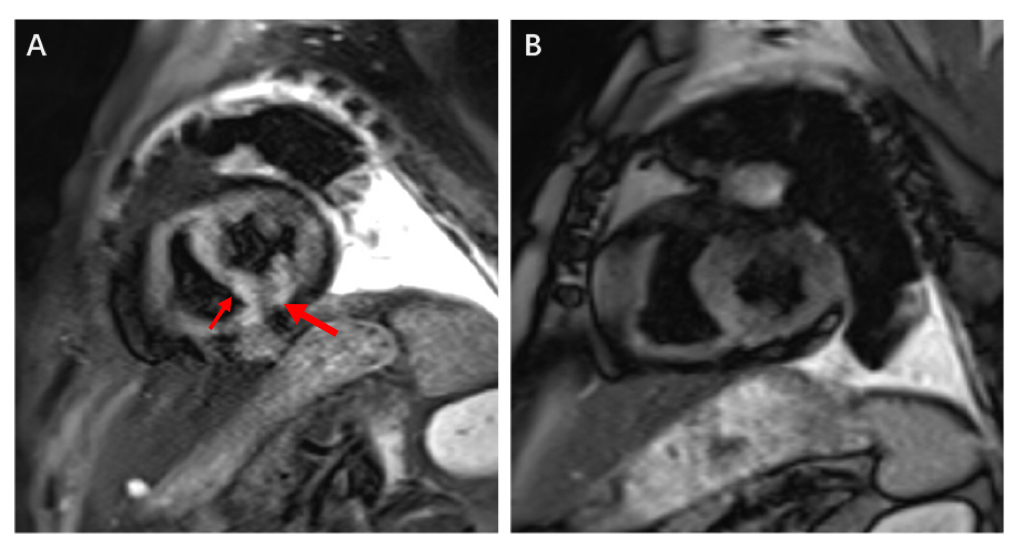

邓阿姨是“入住”过心胸整合病房的患者,她与肿瘤的抗争已持续近十年。但在一次常规治疗前,检查发现她的心肌肌钙蛋白突然显著升高,还出现了严重的室性早搏和短阵室速,随时可能恶化为室颤或心脏骤停。韩文正副主任凭借丰富经验,迅速判断这是免疫检查点抑制剂相关性心肌炎,致死率极高!于是,团队采用进行大剂量激素冲击治疗,用药第二天,患者的心肌酶水平就开始下降,六周后心脏磁共振显示心肌水肿已基本消失。现在,邓阿姨仍继续在医院接受后续的抗肿瘤治疗,病情平稳。